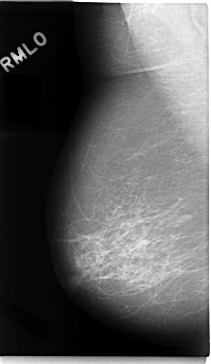

C_0018_1.RIGHT_MLO

RIGHT_CC LINES 4688 PIXELS_PER_LINE 2832 BITS_PER_PIXEL 12 RESOLUTION 50 NON_OVERLAY

RIGHT_MLO LINES 4720 PIXELS_PER_LINE 2736 BITS_PER_PIXEL 12 RESOLUTION 50 NON_OVERLAY